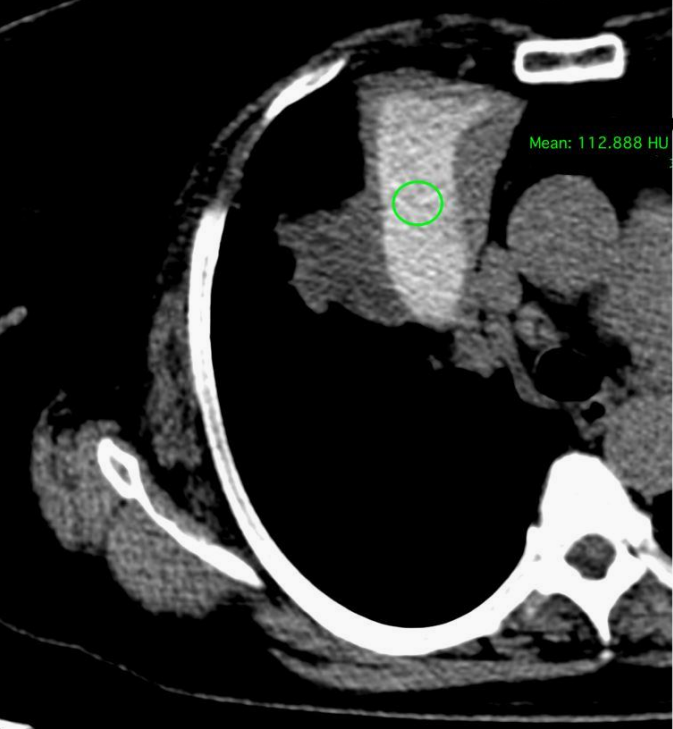

胸部CT:中央支气管扩张(圆柱状支气管扩张)(图2),扩张支气管内可见均匀高密度区,可能为高密度黏液影(hyperattenuating mucus,HAM)(图3、4),周围可见吸收性/阻塞性肺不张,累及双上叶和右中叶。肺门周围区域中央段支气管近端变窄(可能因黏液堵塞而继发),双肺上叶可见少量大小不一的小叶中心结节。结合以上,其影像学表现与变应性支气管肺曲霉病(Allergic Bronchopulmonary Aspergillosis,ABPA)相符。

图3 非增强CT示中央支气管扩张,其内可见均匀高密度区/集合(白色箭头),可能为HAM

图4 非增强CT示扩张支气管内平均HU~ 112的HAM